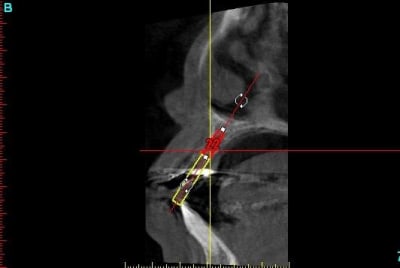

pour ceux que ça intéressent, une petite utilisation d'expansion de la paroi palatine, sur une avulsion d’incisive(racine fendue). toutes mes excuses pour la mauvaise qualité des photos.